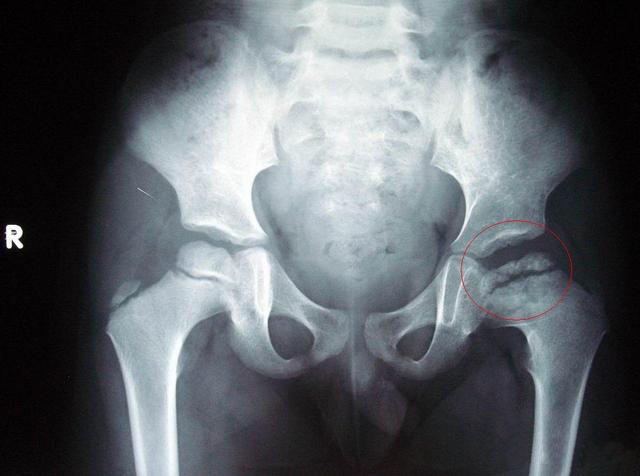

老年妇女x线照片显示髋关节退行性改变,右侧髋关节缺血性坏死